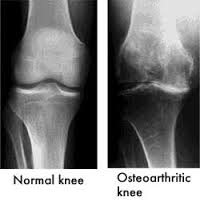

Osteoarthritis is the most prevalent form of knee arthritis, often referred to as “wear-and-tear” arthritis. This degenerative joint disease occurs when the cartilage cushioning the ends of the bones in the knee gradually deteriorates. As the cartilage wears away, the bones begin to rub against each other, leading to pain, swelling, and decreased joint function.

• X-rays: To identify changes in bone structure and joint space narrowing.